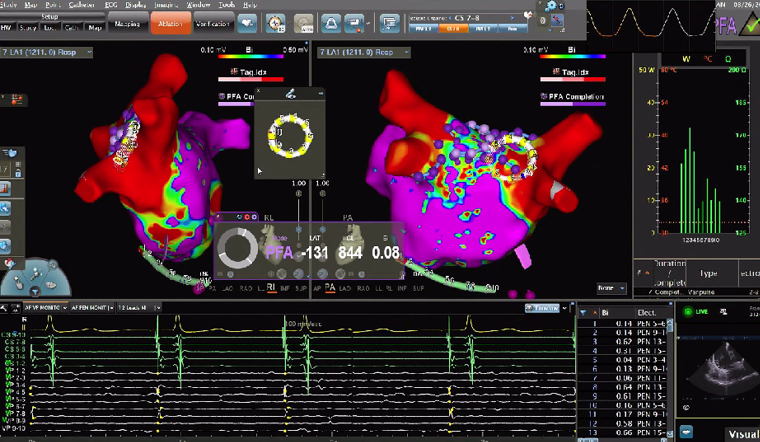

VARIPULSE作为首款搭载Carto三维平台的脉冲消融产品,自上市以来,凭借其“高效”、“绿色”与“贴靠”三大核心价值,赢得了国内专家的广泛认可。上市百日内,已成功服务近七百位中国患者,实现近100%的即刻手术成功率,平均消融时间仅35分钟,且超过20%的手术在零射线条件下完成。凭借这一卓越的临床表现,VARIPULSE不仅为医疗工作者提供了更先进、更全面的治疗方案,也为广大患者带来了恢复窦性心律的新希望。

在本次电生理手术直播周期间,20位资深术者通过实时手术演示,全方位展现了 VARIPULSE脉冲消融系统在房颤治疗中的高效与绿色优势,将其临床性能推向极致。手术数据亮眼——全场直播的平均消融时间仅28分钟,充分印证了该系统的高效性;学术交流同样热烈,超50位领域专家齐聚线上,围绕‘麻醉方案优化’‘、“术式创新选择”、”并发症预防策略”等脉冲电场消融领域的核心热点话题,展开深度研讨与观点碰撞。

在PFA房颤手术中,三维很重要,可以帮助判断贴靠怎么样,寻找哪里有gap,同时现在是绿色电生理时代,只有三维才能做到绿色。PFA房颤手术中穿刺需要偏前偏低,结合ICE的穿刺能够使可调弯鞘管配合PFA导管在右下肺贴靠更好。术中肝素补足很重要,ACT300以上能大大减少无症状脑损伤等并发症。